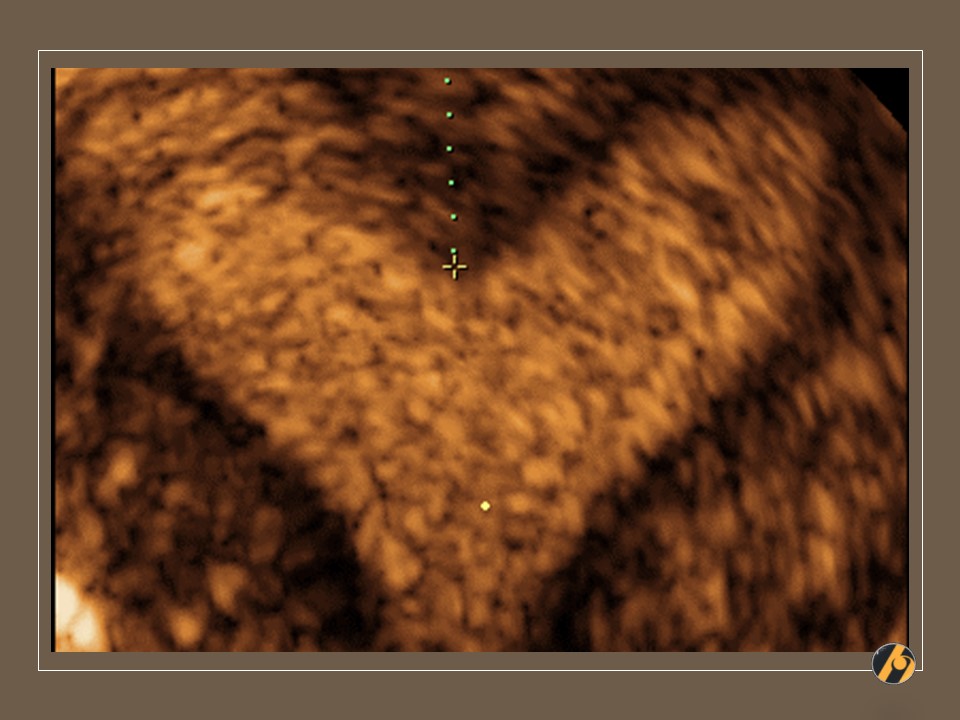

3D rekonstrukcija materične šupljine

Ultrazvučna slika predstavlja 3D rekonstrukciju maternične šupljine, pri čemu se uočava centralno postavljena duboka pregrada maternične šupljine, koja se pruža do donjeg uterinog segmenta gdje se završava prije nego je dosegnula vrat maternice. Obje maternične šupljine međusobno komuniciraju preko manjeg nepregrađenog dijela neposredno iznad vrata maternice. Fundus je zaravnjen, po čemu se slika pregrađene maternice razlikuje od dvoroge maternice. Prije planiranja trudnoće, nužna je resekcija septuma.